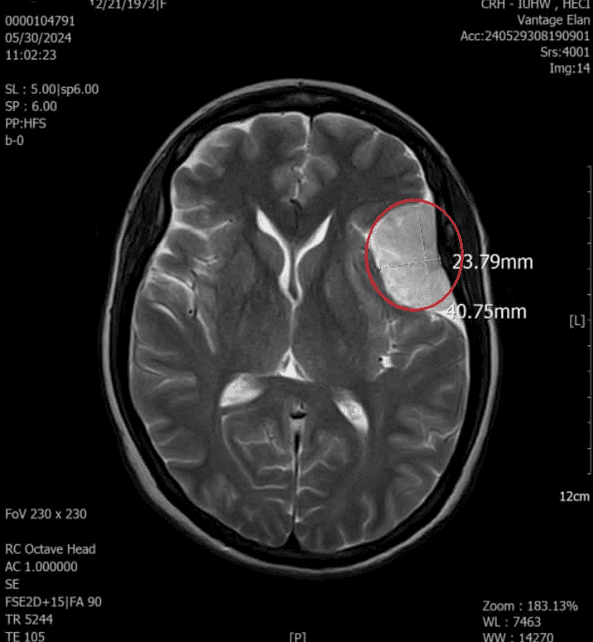

MRI DWIBS (Diffusion-weighted Whole Body Imaging with Background Suppression) là kỹ thuật chụp cộng hưởng từ khuếch tán toàn thân xóa nền, cho phép tầm soát toàn bộ cơ thể trong một lần chụp. Phương pháp này được ứng dụng hiệu quả trong tầm soát ung thư, phát hiện di căn và theo dõi tiến triển bệnh. So với các phương pháp chẩn đoán hình ảnh khác, MRI DWIBS sở hữu nhiều ưu điểm như: không nhiễm xạ, không cần tiêm thuốc cản quang, thời gian chụp toàn thân rất kỹ từ 50đến60 phút, người bệnh có thể sinh hoạt bình thường ngay sau khi thực hiện và phù hợp với cả người mắc bệnh đái tháo đường. Tuy nhiên, một số trường hợp không được chỉ định chụp MRI DWIBS, bao gồm người đang mang máy tạo nhịp tim, có mảnh đạn, mảnh kim loại gần mạch máu lớn hoặc các cấu trúc nguy hiểm, các dụng cụ cấy ghép trong cơ thể… Những trường hợp này cần thông báo đầy đủ với bác sĩ trước khi thực hiện chụp chiếu.